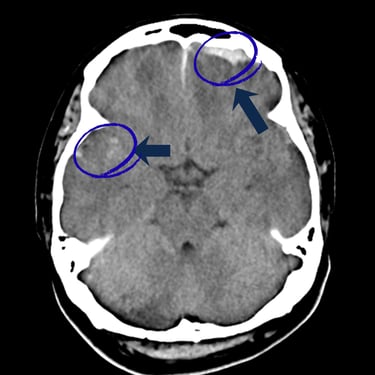

El trauma craneal severo es una de las principales emergencias neurológicas y puede poner en riesgo la vida del paciente. El diagnóstico por imágenes, a través de tomografía computarizada o resonancia magnética, es fundamental para identificar hemorragias, fracturas o lesiones cerebrales y definir el tratamiento adecuado. La evaluación temprana y la intervención oportuna por parte del neurocirujano permiten reducir complicaciones y mejorar el pronóstico neurológico. Una atención especializada y multidisciplinaria resulta esencial para garantizar la recuperación y preservar las funciones cerebrales.